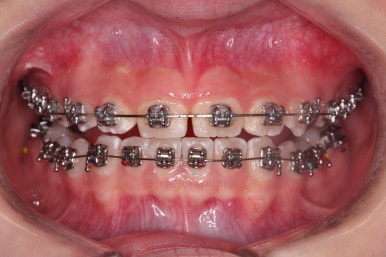

우선 윗니에만 교정장치를 부착했습니다.

성장치료라더니 교정치료? 하실 수 있지만 윗니를 가지런하게 해준 이유는 아래턱을 앞으로 성장시켜줄려니 윗니 앞니가 옥니처럼 가로막고 있어서 아래턱이 앞으로 나올래야 나올 수 없는 상황이었어요.

그래서 앞니의 각도를 먼저 개선해주기로 했죠.

일반적인 교정장치이긴 하지만 그 목적이 달랐던 거에요.

앞니의 각도가 앞으로 살아난 것이 보이실 거에요.

자연스럽게 과개교합 경향도 개선되어 어금니로 물었을 때 아래 앞니가 점점 보이기 시작하네요.